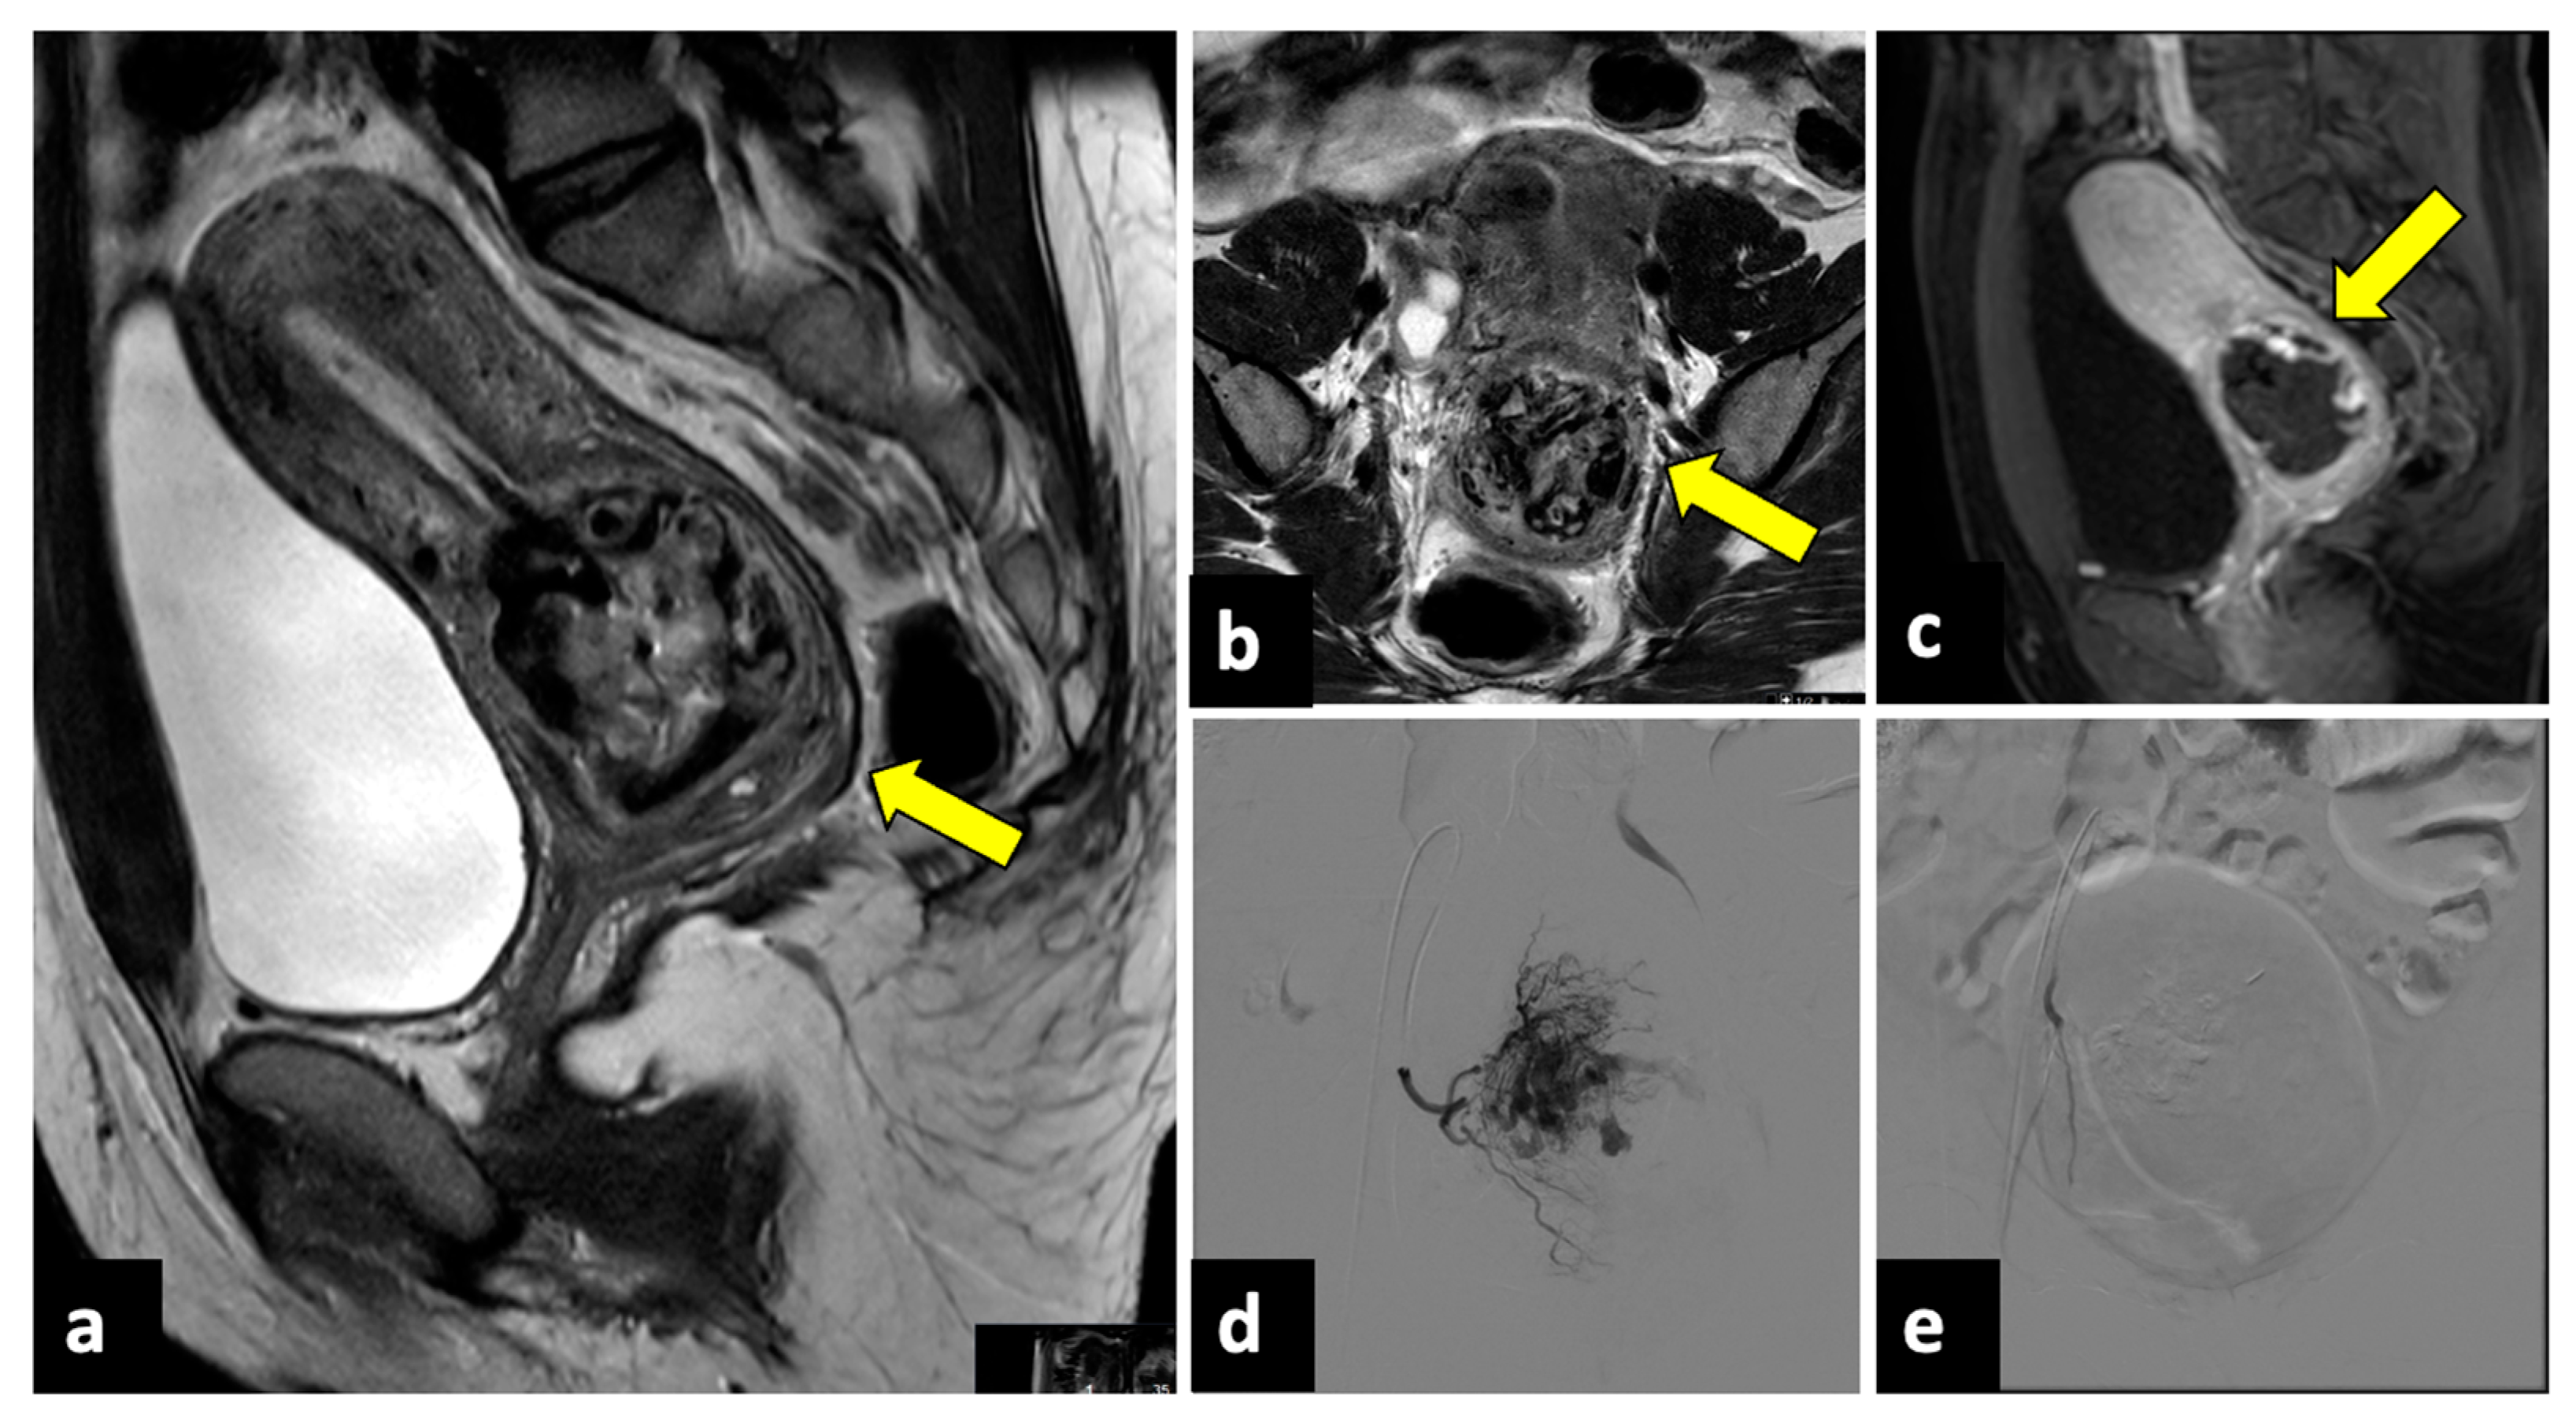

Figure 11.

Ruptured cervical ectopic pregnancy in a thirty-three-year-old patient who presented at the emergency department with acute pelvic pain and severe vaginal bleeding. MRI sagittal (a) and axial (b) T2-weighted, and sagittal T1-weighted early contrast-enhanced fat-saturated (c) images show an empty uterine cavity and a ruptured ectopic pregnancy within the cervical canal (yellow arrows). This patient was managed with uterine arteries embolisation. Preprocedural images (d) show a hypervascular area in the region of the cervical ectopic pregnancy that is supplied mainly by the right uterine artery. Post-embolisation (e) arteriogram demonstrates complete stasis.